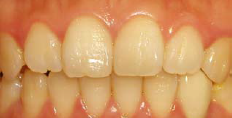

女性,22 岁, 现病史:外伤致33 脱落1 周后求诊,要求种植修复 既往史:无特殊

左下3缺失,牙龈略红肿,近远中距离可,对颌无伸长 X线示牙槽窝内空虚

术区常规消毒铺巾,碧蓝麻阻滞加浸润麻醉,牙槽脊顶切开翻瓣,尖钻定位,逐级备洞,植入牙槽窝清创后预备植牙窝,植入种植体(Replace Select®,4.3 mm×13 mm),唇侧缺损处填充自体骨屑。拧上愈合基台,穿龈愈合,严密缝合,常嘱术后4个月后复诊取模,2周后戴牙